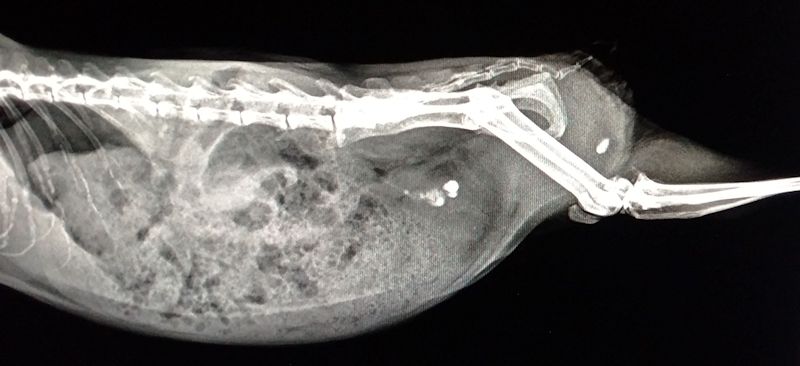

| Blasensteine sind auf dem Röntgenbild deutlich zu erkennen. | |

| Der Stein rechts hinten sitzt in der Harnröhre, die restlichen in der Mitte sind in der Blase. Im vorliegenden Fall wurde der hintere Stein unter Betäubung ausmassiert. Ein weiterer nach ~ 2 Wochen. Weitere 2 Wochen später musste das Schweinchen eingeschläfert werden. Es hatten sich 4 bis 5 neue Steine gebildet, beim Wasserlassen war der Urin blutig und innerhalb von 2 Tagen hat sie ~110g an Gewicht verloren. | |